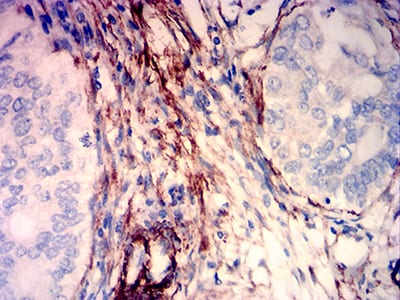

分类: 科研抗体货号: 31765别名: CDM; HCAD; LCAD; H-CAD; L-CAD; NAG22应用: IHC,FCM反应种属: Human